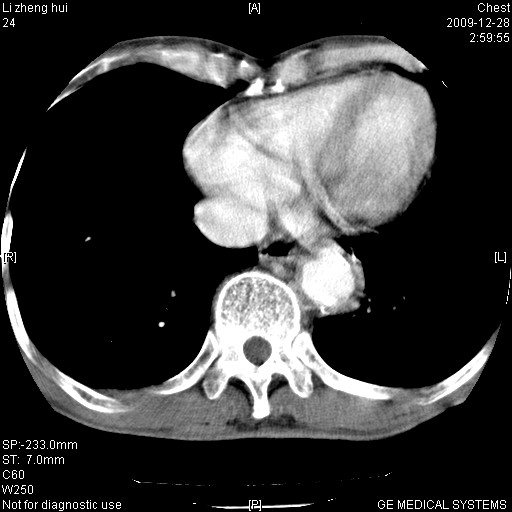

标题: CT23859:胸主动脉瘤 [打印本页]

标题: CT23859:胸主动脉瘤

男  79岁 胸部痛急诊入院,晚上做的增强

考虑主动脉瘤?(增粗、钙化、壁血栓?)

动脉瘤伴附壁血栓

1)考虑胸主动脉壁间血肿或夹层动脉瘤。2)多发性肝囊肿。

1)考虑胸主动脉附壁血栓或夹层动脉瘤。2)多发性肝囊肿。